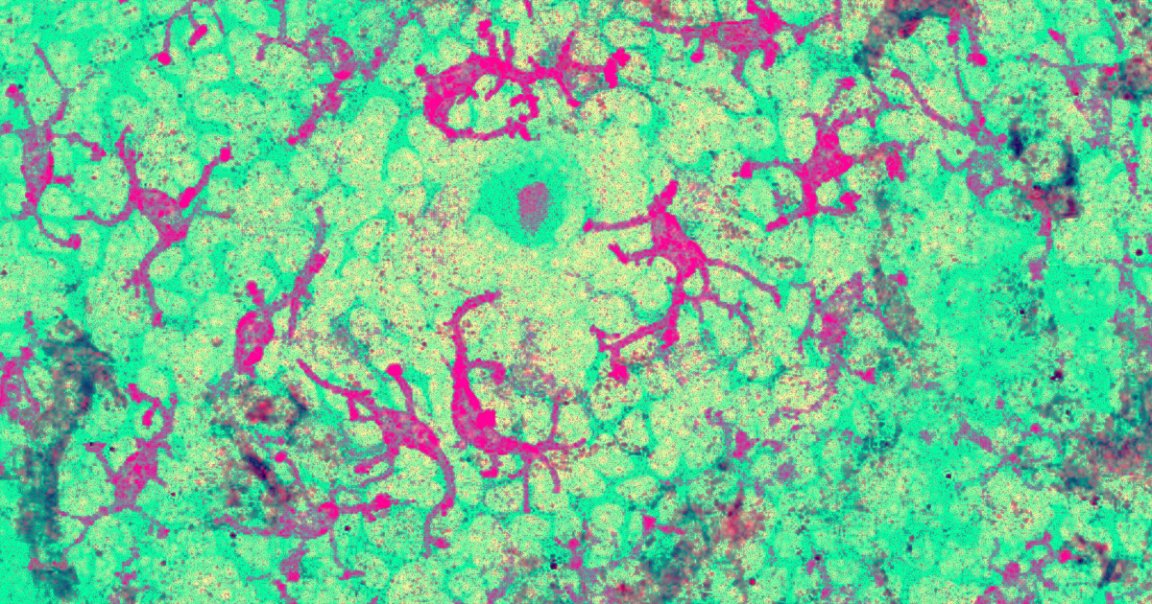

On Monday, researchers from Cardiff University published a new study in the journal Nature Immunology detailing their discovery of a T-cell equipped with a new type of T-cell receptor (TCR) that recognizes a molecule called MR1.

This molecule appears on the surface of many types of cancer cells as well as healthy cells, but T-cells equipped with this TCR know to kill only cancer cells.